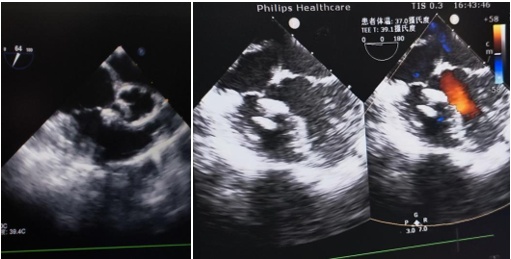

与传统开胸手术或需要在X光下操作的手术不同,这次手术全程只用超声引导,完全没有辐射,切口也仅不到2厘米,不损伤胸骨。植入的“补片”精准封堵了心脏的缺损,术后超声显示“小洞”补得非常完整。

术后随访显示封堵器无移位,未见残余分流,有力验证了全超声引导下经胸小切口全降解室缺封堵术在儿童先心病微创治疗中的安全性和有效性。目前,两名患儿术后恢复情况良好,仍在长期随访,关注患儿术后远期状态。

术后患儿超声复查显示,封堵完全,无残余分流